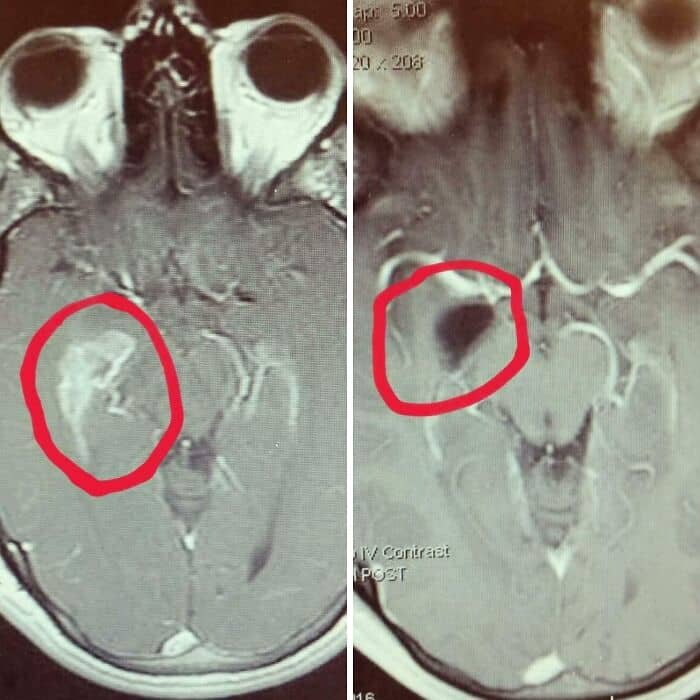

#39 My Brain Before And After Brain Surgery

#27 The Size Of Earth Compared To The Size Of The Rings Of Saturn